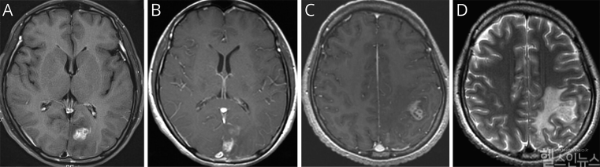

이번 연구는 서울대병원에 내원한 40대 여성 환자를 대상으로 이뤄졌다. 환자는 심한 두통과 구토 증세로 병원을 방문했으며, 초기 뇌 MRI에서 좌측 후두엽에 불규칙하게 조영된 종양성 병변이 발견돼 뇌종양이 의심됐다. 의료진은 수술을 권유했지만, 환자는 증상이 일시적으로 호전되자 치료를 거부하고 퇴원했다.

7개월 후, 환자는 다시 극심한 두통과 전신 발작으로 병원을 방문했다. 후속 MRI에서 병변이 좌측 후두엽에서 좌측 두정엽으로 이동한 것이 확인됐고, 이 병변 이동은 스파르가눔증의 대표적인 진단 단서가 됐다.